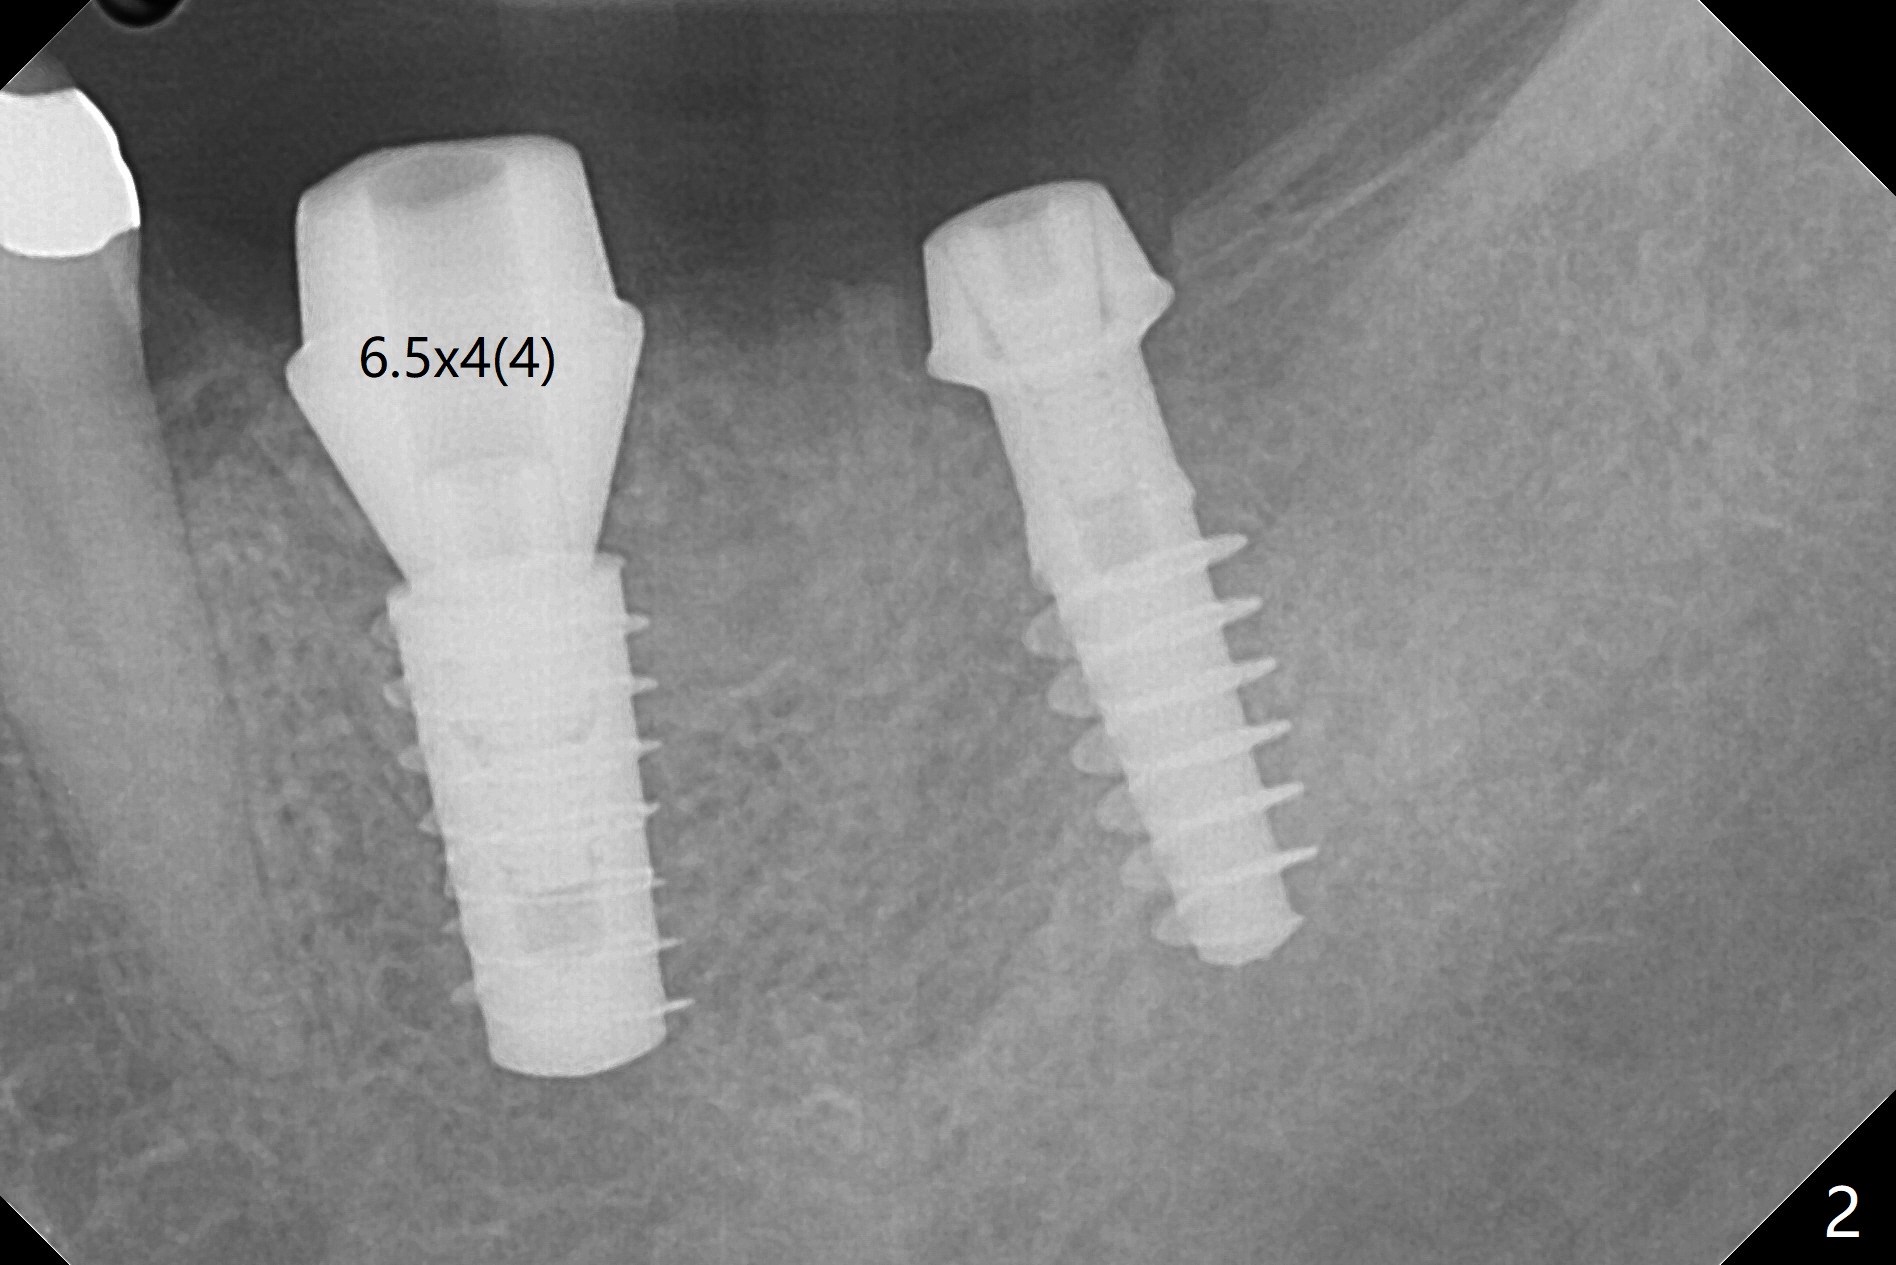

After osteotomy according to drill sequence except no tap at #18, a 5x9 mm FC at #19 achieves insertion torque at 20 Ncm, while a.4.5x9(3) mm Magicore <10 Ncm (Fig.1,2), probably due to the fact the core (middle portion) of Magicore is small, dictating underprep (in diameter) when the bone is not hard. In addition, IS implant driver cannot be engaged to Magicore so that the placement of the latter is free hand. Because of supraeruption of the opposing teeth, the abutment at #19 is heavily reduced, whereas the Magicore is placed super low (Fig.2). The latter may be backed up or crown lengthening is necessary. In fact neither is necessary, since there is crestal bone loss at #18 nearly 3 months postop (Fig.3 *). There is no difficulty in placing 4.5 mm healing cuff.